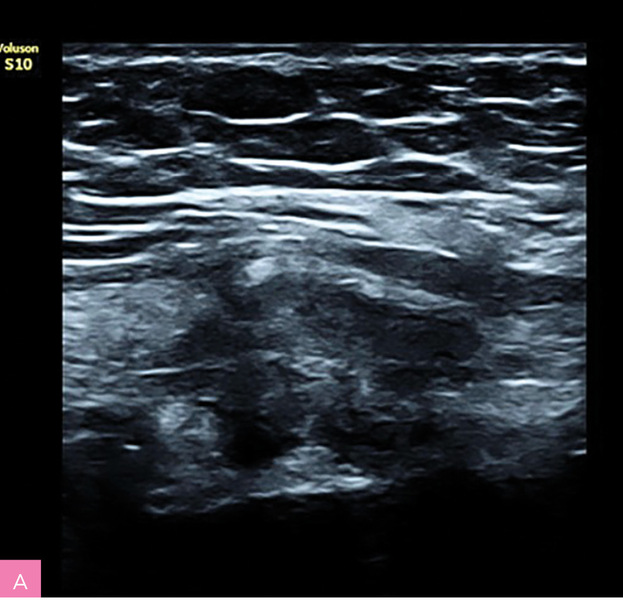

Rycina 1A, B. Obraz ultrasonograficzny zmiany endometrialnej powłok brzucha z typowymi spikularnymi brzegami (materiał własny autorki)

Charakterystyka wszczepów endometrialnych powłok brzucha (tab. 2; ryc. 1, 2):

- zmiany w większości hipoechogeniczne i heterogenne

- średnica zmian wynosi między 5 mm a 5 cm, chociaż mogą osiągać znaczne rozmiary

- zmiany mają charakterystyczny spikularny (naciekający) obwód lub miejscowo nieregularny margines

- małe torbielowate obszary, głównie położone obwodowo – obraz drobnych torbieli krwotocznych, dające cień akustyczny

- obwodowe cechy włóknienia – hiperechogenna otoczka wokół guza.